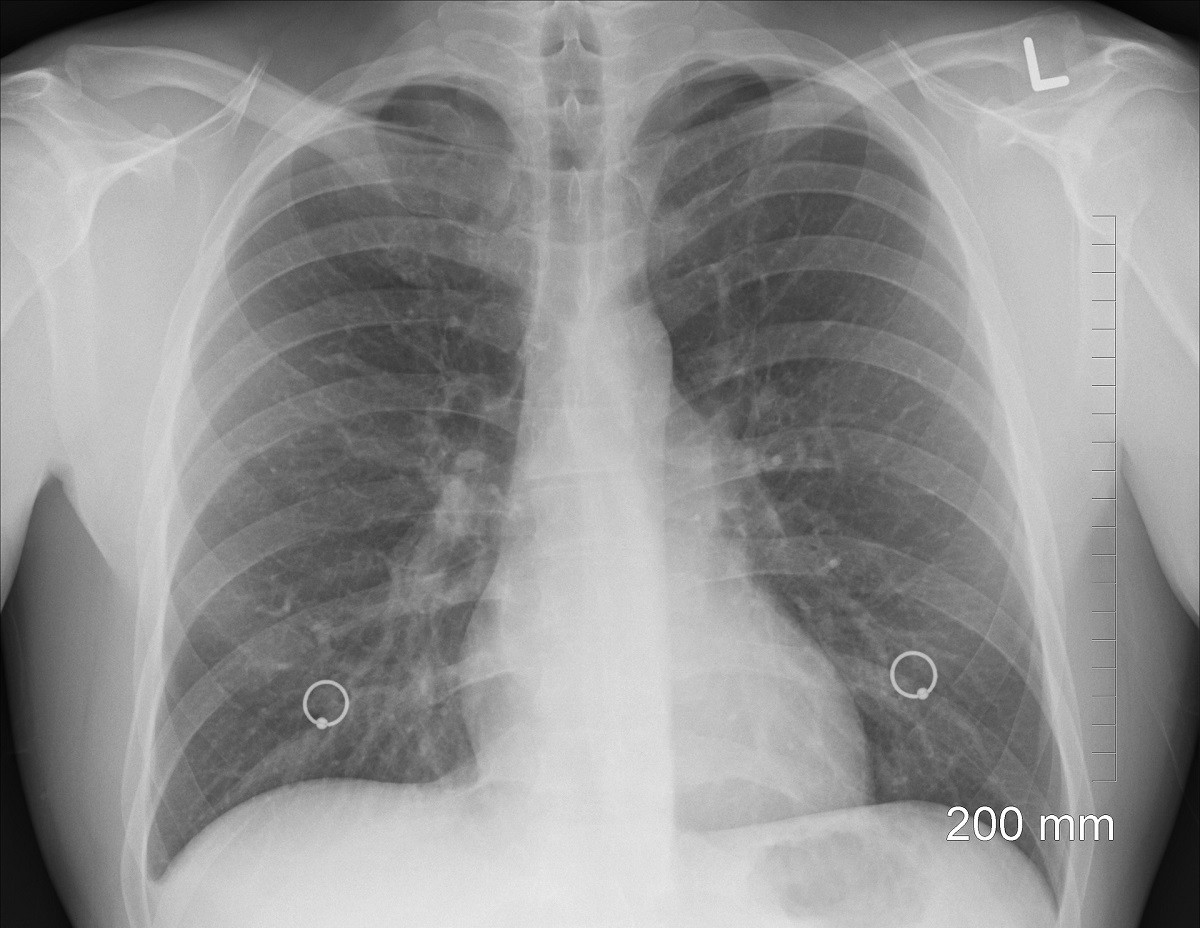

La Sindrome da anticorpi antifosfolipidi può provocare trombosi arteriosa o venosa o a livello dei capillari, in qualsiasi organo. Colpiti soprattutto sono i reni, fegato, polmoni e cervello. Questo significa che si manifestano occlusioni dei vasi, collegati a tromboembolismo (il trombo può frammentarsi e produrre emboli che possono spostarsi e occludere vasi più piccoli: embolo, trombo e coagulo, infatti, non sono proprio la stessa cosa).

- embolia polmonare

Una ristretta percentuale di pazienti che soffrono di questa patologia (soprattutto donne) possono sviluppare trombosi diffuse su più organi, con occlusione di piccoli vasi. Quando questo accade a livello cerebrale, ecco che si parla di Sindrome catastrofica da anticorpi antifosfolipidici. Tuttavia questa sindrome può provocare anche insufficienza respiratoria. La diagnosi differenziale, in tal caso, va fatta con: